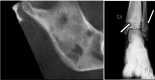

Case presentation: We describe the clinical manifestations, radiological pictures and disease course of other causes of limping in childhood, through a case series of seven cases and a brief discussion of each disease.

Conclusions: although trauma is the most common cause of acute limping, when there is no history of traumatic events and the limping has a chronic course, Juvenile Idiopathic Arthritis is usually the most likely clinical diagnosis. However, other some rare conditions should be taken into account if JIA is not confirmed or if it presents with atypical clinical picture.

Keywords: CACP syndrome; COPA syndrome; Chronic nonbacterial osteomyelitis; Differential diagnosis; JIA; Limping child; Lyme arthritis; Neuroblastoma; Non-traumatic limping; Pigmented villonodular synovitis.